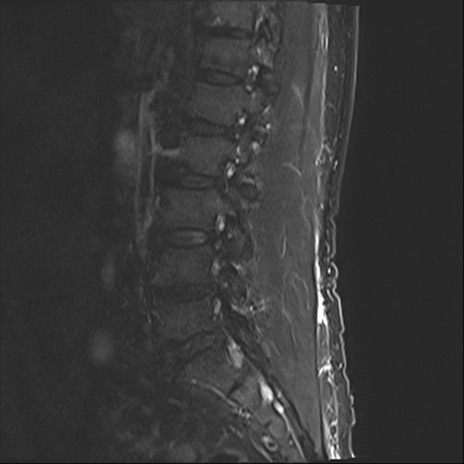

【整形】TIPS症例2 腰椎MRI STIR(矢状断像)

【症例】70歳代男性

【主訴】左下肢痛

【現病歴】2週間前くらいから腰痛、左下肢痛あり。左臀部から大腿、下腿外側のしびれが常時ある。歩行とともに同部位の痛みあり。

【身体所見】Lasegue70-/60+、Bragard-/±、PTR ±/±、ATR -/-、IP 5/5、TA 5/4、TS 5/5、EHL 右第1足趾なし/3、FHL 5/5、hypersthesia(-)、足背動脈触知良好

異常所見と診断は?